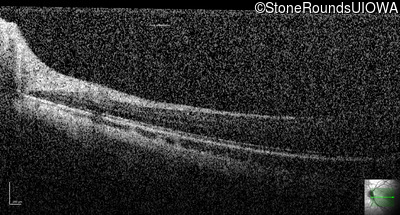

Optical Coherence Tomography - Right - 20/2000

Exemplar / OCT Stack